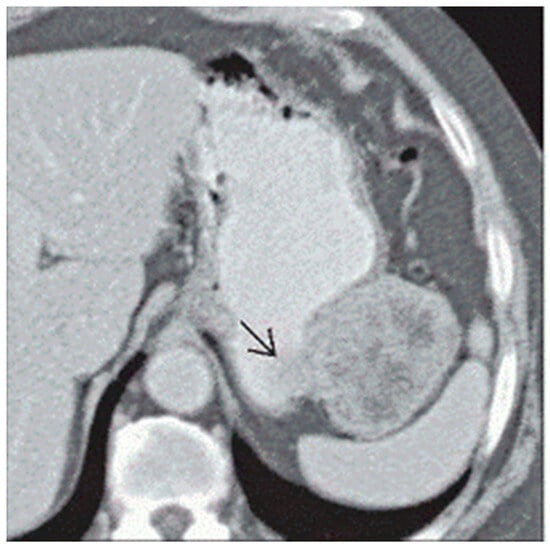

Gastric GISTs are often identified first in computerized tomography (CT) scans, either incidentally or in the targeted workups of symptoms. Intravenous contrast use allows for improved detection, particularly of smaller masses, but it is also valuable for discerning gastric GISTs from other gastric tumors. While tumors measuring <5 cm can be homogeneous and well circumscribed, larger gastric GISTs (or those with aggressive phenotypes) have irregular borders. Masses of >5 cm may demonstrate necrosis, calcifications, or cystic portions (Figure 1) [13]. Given the relatively consistent nature of the characteristics of gastric GISTs in CT imaging, a practical scoring guideline was published to readily differentiate GISTs from other subepithelial tumors. In addition to the features noted above, a patient age greater than 49 years old, lower attenuation on unenhanced images (<43 HU), a non-cardia location, and the absence of enlarged lymph nodes were included in the algorithm [14]. After studying 64 patients and employing a validation cohort of 92 patients, the accuracy of diagnosing gastric GISTs in CT imaging alone using the scoring algorithm was 92% with a sensitivity of 100%, and a score of greater than or equal to 4 was found to accurately predict GISTs in all but one case [14].

Figure 1. Arrow pointing to a heterogeneous, irregular bordered gastric GIST located on the greater curvature of the stomach abutting the splenic hilum [13].